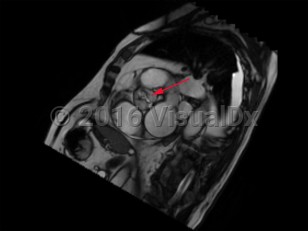

Aortic stenosis (AS) is the narrowing of left ventricular outflow through the aortic valve. It is the most prevalent cause of ventricular outflow obstruction, and it is increasing in prevalence as the population ages and life expectancy increases. While patients are generally asymptomatic in the presence of mild outflow obstruction, exertional dyspnea, chest discomfort, fatigue, dizziness, and syncope develop as the degree of obstruction progresses.

Contributing etiologies include calcification of the aortic valve cusps (most common in the elderly population), congenital abnormalities (ie, bicuspid aortic valve), rheumatic fever, chest radiotherapy, endocarditis, and alkaptonuria. Potential complications include heart failure, cardiac arrhythmias, infectious endocarditis, pulmonary hypertension, excessive bleeding, stroke, and other embolic events.

There is no known medical therapy available to delay progression of AS. Patients should be monitored carefully with serial clinical evaluations and echocardiography in order to determine if and when aortic valve replacement is needed, which may be performed by surgical aortic valve replacement or transcatheter aortic valve replacement (TAVR), also known as transcatheter aortic valve implantation (TAVI). Prolonged or intense physical activity and competitive sports should be avoided in patients with severe AS.